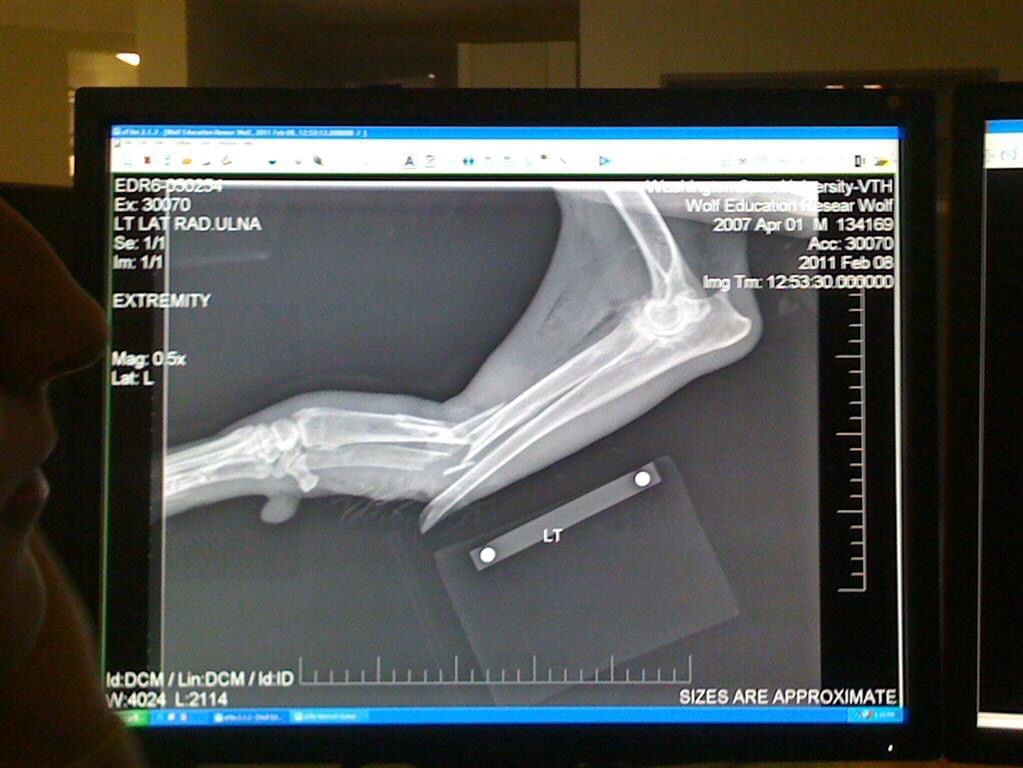

The highlight was definitely the surgery of a wolf that needed an amputation of his front leg.